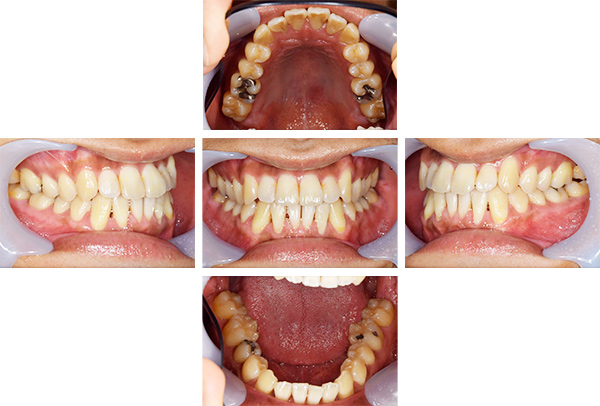

歯列矯正・インレー・クラウン症例

前歯が黒っぽいのが気になる、

悪いところは全部治したい

年齢 54代女性

主訴 歯をきれいにしたい

治療

期間

4年

費用 セラミックインレー 12本

660,000円

オールセラミックプレミアムクラウン 3本

495,000円

矯正 874,900円

計 2,029,900円(税込)

症例写真(治療前)

治療前:

八重歯が目立ちます。また銀歯もおおく、見た目が気になります。虫歯も散見できます。

担当医師所見

矯正装置をつけています。だんだん八重歯が動いてきているのがわかります。今回のケースでは、抜歯を行わずに矯正ができました。

症例写真(治療後)

治療後:

矯正治療と虫歯の治療すべて終わったときの写真になります。見た目も最初の頃とは全く違いますし、お口の中もすごく綺麗です。

方針

まずは虫歯の治療を行い、被せ物をする部分は仮歯をいれて矯正を行う。矯正終了後、仮歯の部分を最終的な被せ物に変えていく。また気になっていた銀歯もセラミックに変えて終了となった。

内容

セラミックインレー、オールセラミックプレミアム、矯正

特記

事項

虫歯の治療によって歯が一時的に染みるようになる可能性があります。また、歯を抜かずに矯正を行っていますが、全ての方で歯を抜かずに矯正ができるわけではありません。

治療リスク・副作用

・詰め物を銀歯からセラミック等のインレーに変えると、歯がしみることがある

・被せ物をやりかえる時は中で大きく虫歯になっていたり、歯が割れている場合は抜歯になることもある

・インプラント治療は骨と結合するのに期間がかかるが、個人差がある

・ホワイトニング後は歯がしみることがある

・詰め物、被せ物をする時は自分の歯を削ることになります